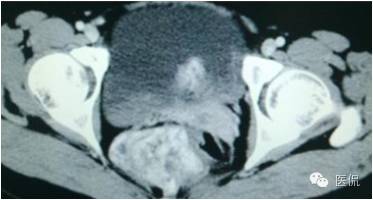

女,37岁,体检超声发现盆腔包块一周。无其他异常。

增强延迟期(CT值106HU)

手术是:盆腔占位,病理为:血管肌纤维母细胞瘤。与肛门粘连,于是同时做了肛门的处理。